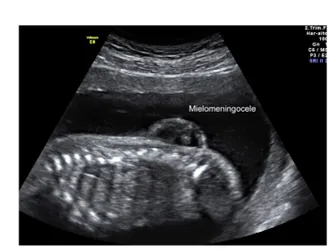

Image

Espina Bífida

Imagen ecográfica correspondiente a  un mielomeningocele. Se evidencia la masa que contiene en su interior los nervios de la médula espinal.

Las características de la ecografía que sugieren una espina bífida incluyen una masa quística en cualquier lugar de la columna. Cuando se trata de un mielocele se evidencia el defecto óseo sin la presencia del saco.